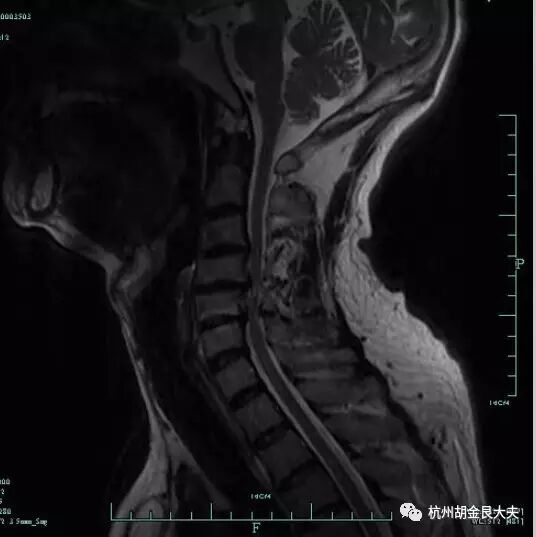

患者颈部疼痛伴右手麻木,MR摄片如下:

请给出诊断:

卷2

选择题:DACDB DBCDC DD

阅片题:

项目 | 评分标准(请酌情打√) | √ | 分值 |

读片 | C3/4、C4/5、C5/6椎间盘突出(少写一个节段水平扣1分,只答颈椎间盘突出给6分) | 9 | |

颈4/5水平髓内高信号(或写颈髓损伤) | 1 | ||

总分 10 | |||